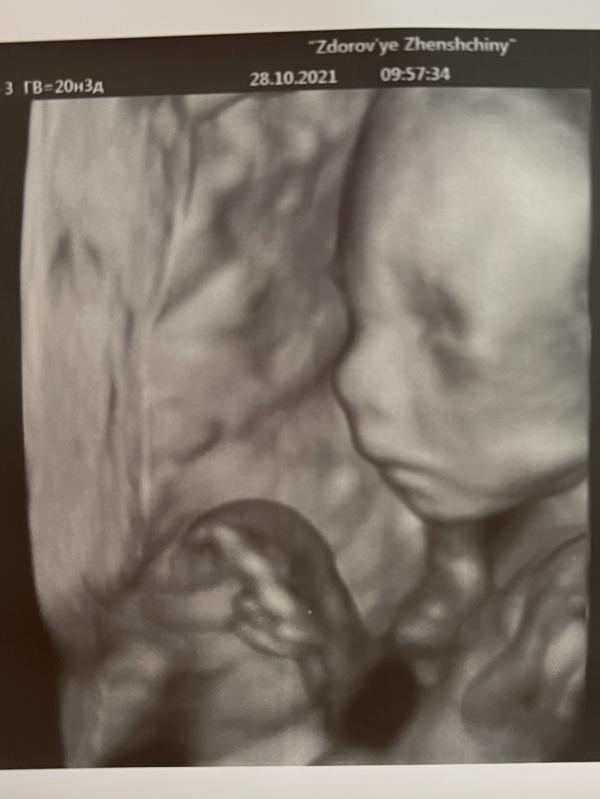

💙 Наш второй скрининг 💙

-Подтвердили пол (мальчик)

-По размерам и развитию все хорошо)

-ПДР на 11 марта 2022г.

-Предположили ранее старение плаценты (назначили УДС сосудов в 24-26 недель)

Делала в здоровье женщины на Кирова. Врач Курило- мне она очень нравится)